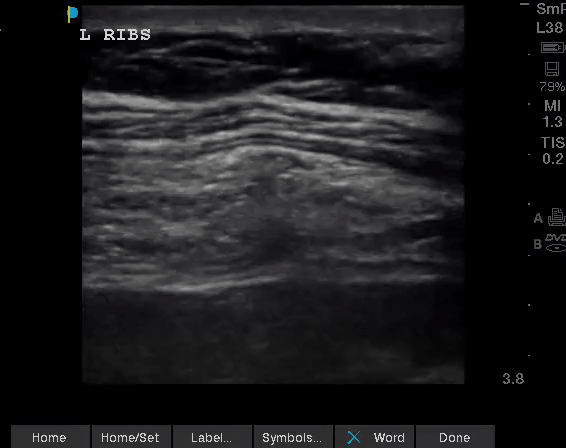

Sono of the Week: 6/1/23

Rib

Fracture